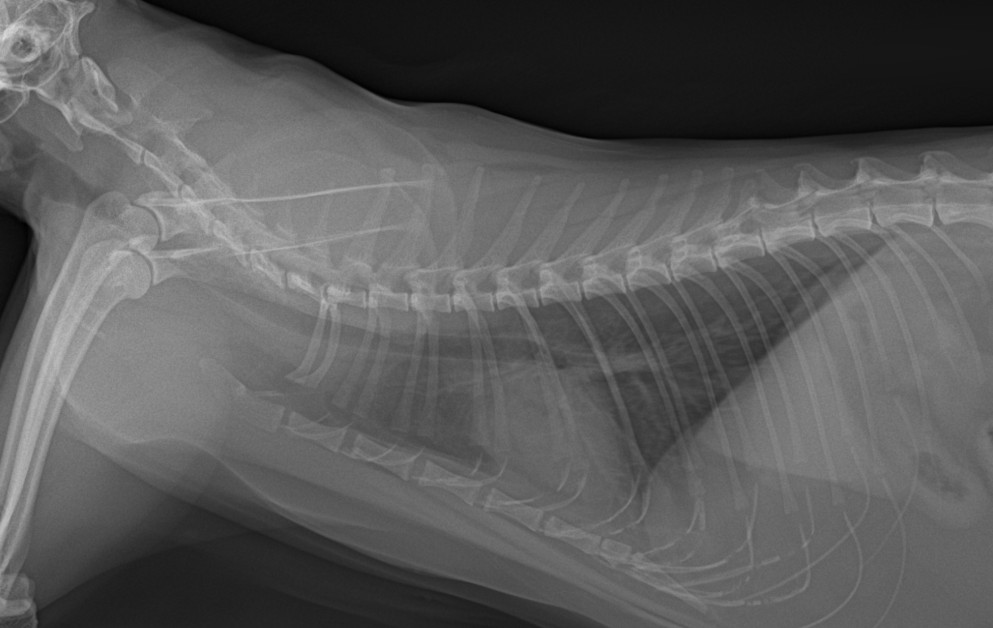

혈액검사에서는 주요 장기 수치, 염증 수치, 전해질 균형 등을 확인했고, X-ray는 흉부·복부 전반의 장기 구조를 점검했습니다. 초음파는 장기 실질 구조나 미세한 이상까지 확인할 수 있어 검진의 핵심 항목으로 포함됩니다. 치과검사는 일반적으로 마취가 동반되어, 구강전용 엑스레이 촬영을 해야 정확한 판단이 가능하지만 치과전문 병원인 만큼 육안으로 기본적인 검사는 해드리고 있습니다.